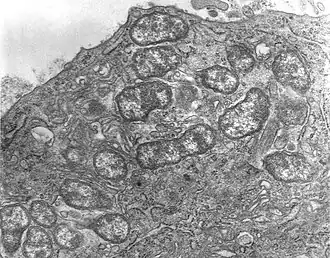

| Фотография микропрепарата Orientia tsutsugamushi | |

Возбудитель — Orientia tsutsugamushi (ранее R. tsutsugamushi, R. orientalis). Возбудитель обладает теми же свойствами, что и другие риккетсии. Антигенная структура O. tsutsugamushi позволяет выделить ряд сероваров: Gilliam, Karp, Kato, Fan. Все штаммы различаются по вирулентности и по антигенным свойствам. Есть штаммы, убивающие 80—100 % подопытных белых мышей, и штаммы, которые обусловливают у них только легкие клинические проявления. Риккетсии нестойки во внешней среде, моментально погибают при кипячении. Выделенные в нашей стране штаммы O. tsutsugamushi относятся к серовару Gilliam[5][6].